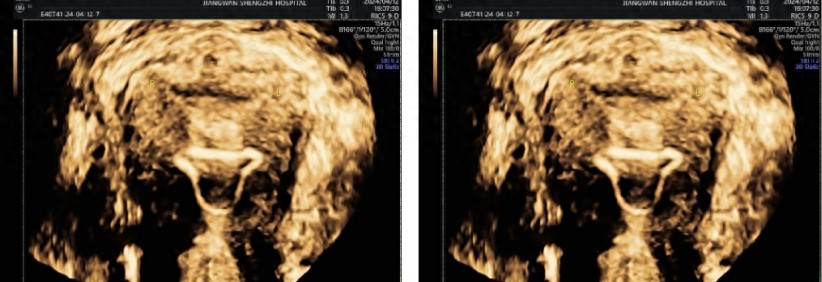

一位处于育龄阶段的女性,其健康状况让人担心。2024年5月24日,是她最后一次来月经的日子。在月经第20天的时候,做了四维彩超,结果显示出不少问题。内膜厚度不均匀,下段大约是2.3mm,中段约为3.1mm,上段约4.7mm。内膜的这种情况不太好,这为后续的诊断以及治疗埋下了隐患。

原来,这位患者在2024年1月的时候,曾在外院做过宫腔镜下宫腔粘连分离术,手术过程中还进行了上环术。然而此次通过四维彩超检查,又发现存在宫腔粘连的可能性,以及宫内节育器下移并嵌顿的可能性。另外,她有剖宫产手术史,由此形成了瘢痕子宫,她在2014年做过剖宫产术,2023年因为脑干胶质瘤出现了特殊情况,不良孕产史给治疗增加了复杂性。

此次检查发现了其他病症,除了之前提到的宫腔粘连和节育器问题。四维彩超显示,子宫后壁下段有稍高回声结节,怀疑是子宫腺肌瘤。子宫前壁下段有低回声结节,考虑是子宫肌瘤(5型)。诊断已经明确,病情比较复杂,多种病症同时存在。